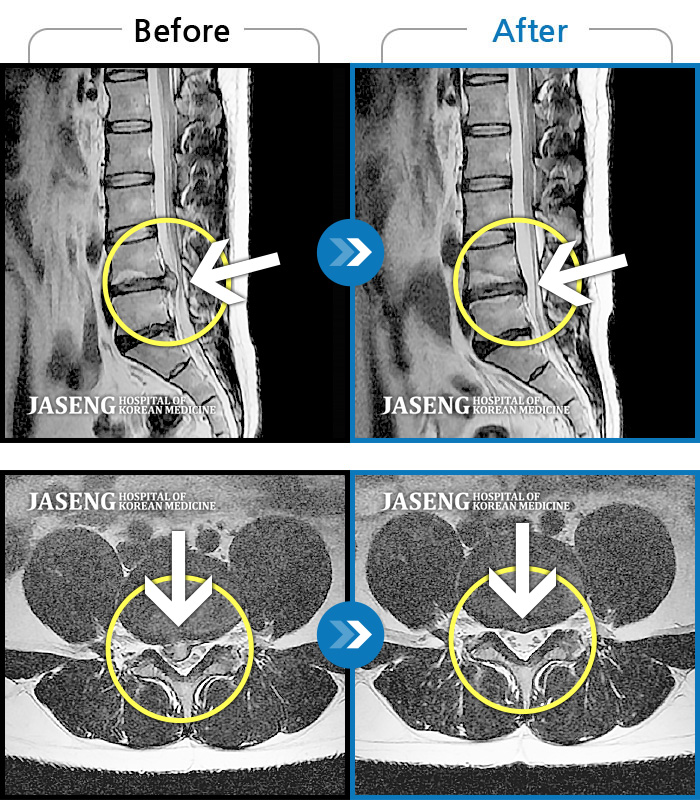

허리디스크

일산 · 김태용 원장

허리와 우측다리가 심하게 저렸다.

촬영시기

2020.05.07 ~ 2020.12.29

허리와 좌측 다리가 당겨 보행이 불가능했다.

2020.02.10 ~ 2021.02.22